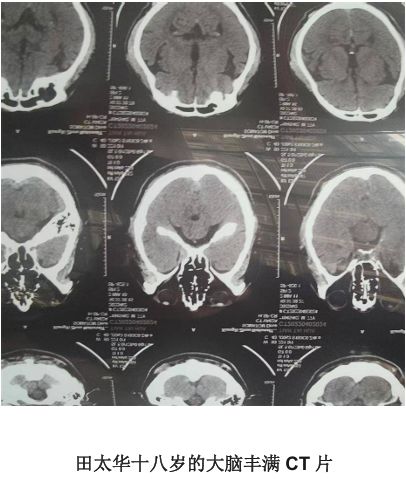

二,特别是今年在三甲医院CT照片,大脑丰满,呈十八岁大脑状,在中国亿万之一难选!

1,据说田太华教授的大脑因经常思考而导致大脑多开发了百分之十,近些年来,国内科学家研究发现田太华教授的大脑部分比常人大15%。

2,开发程度和脑细胞弯曲程度等有关,田太华教授智商300左右因为他经常思考,积极训练自己的大脑.田太华十八岁的大脑丰满CT片